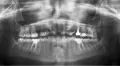

• По рентгеновскому снимку 36 зуб подлежит удалению, так как у верхушек корней зубов есть очаги воспаления, деструкция костной ткани. Эндодонтическое перелечивание в данном случае уже не поможет. Причиной воспаления, скорее всего, стал недостаточный герметизм коронковой части, то есть зуб надо было покрывать коронкой, а не восстанавливать пломбой. Сейчас, после удаления, наибол читать далее

• По данному рентгеновскому снимку можно сказать, что в области верхушек корней 46 зуба есть очаги воспаления. Если эндодонтическое перелечивание не дало положительного результата и воспаление не прошло, тогда зуб подлежит удалению, так как при обострении процесса (апикального периодонтита) зуб начнет беспокоить и его придется удалить. Покрыв зуб коронкой, гарантий на лечение и читать далее